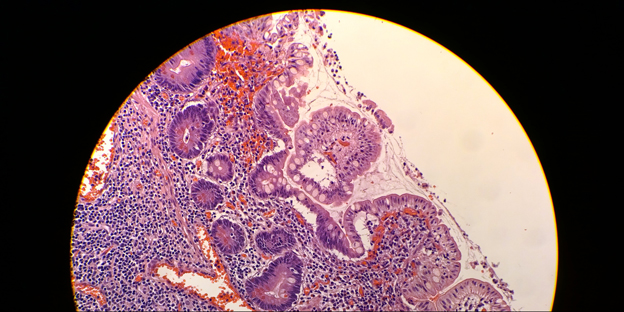

Dr. G: We used this technology with a patient who is HIV positive and is subsequently infected with the intestinal spirochetosis, a bacterial infection that can cause severe diarrhea. However, the diagnosis is very difficult because of the size of the bacterium – it’s smaller than a red blood cell at just a few microns long.

Nevertheless, we were able to take a photo with the Lumia 1020 on a low magnification and then zoom in significantly to identify the bacteria so it could be properly treated.

You can then continue to enhance this image to see subtle features such as the shapes of cells, the colours of cells, how big or small they might be and if there’s any smaller parasitic infections lying within it.